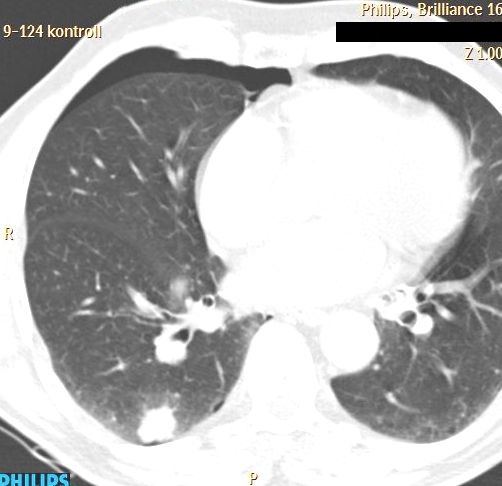

- Ptx (thoracic (figure 14.), mediastinal, infraclavicular, in case of subdiaphragmatic intervention),

Image

A

B

Figure 14. – PTX after lung biopsy (A: immediately after biopsy is only a small PTX, B: 5 minutes CT control)